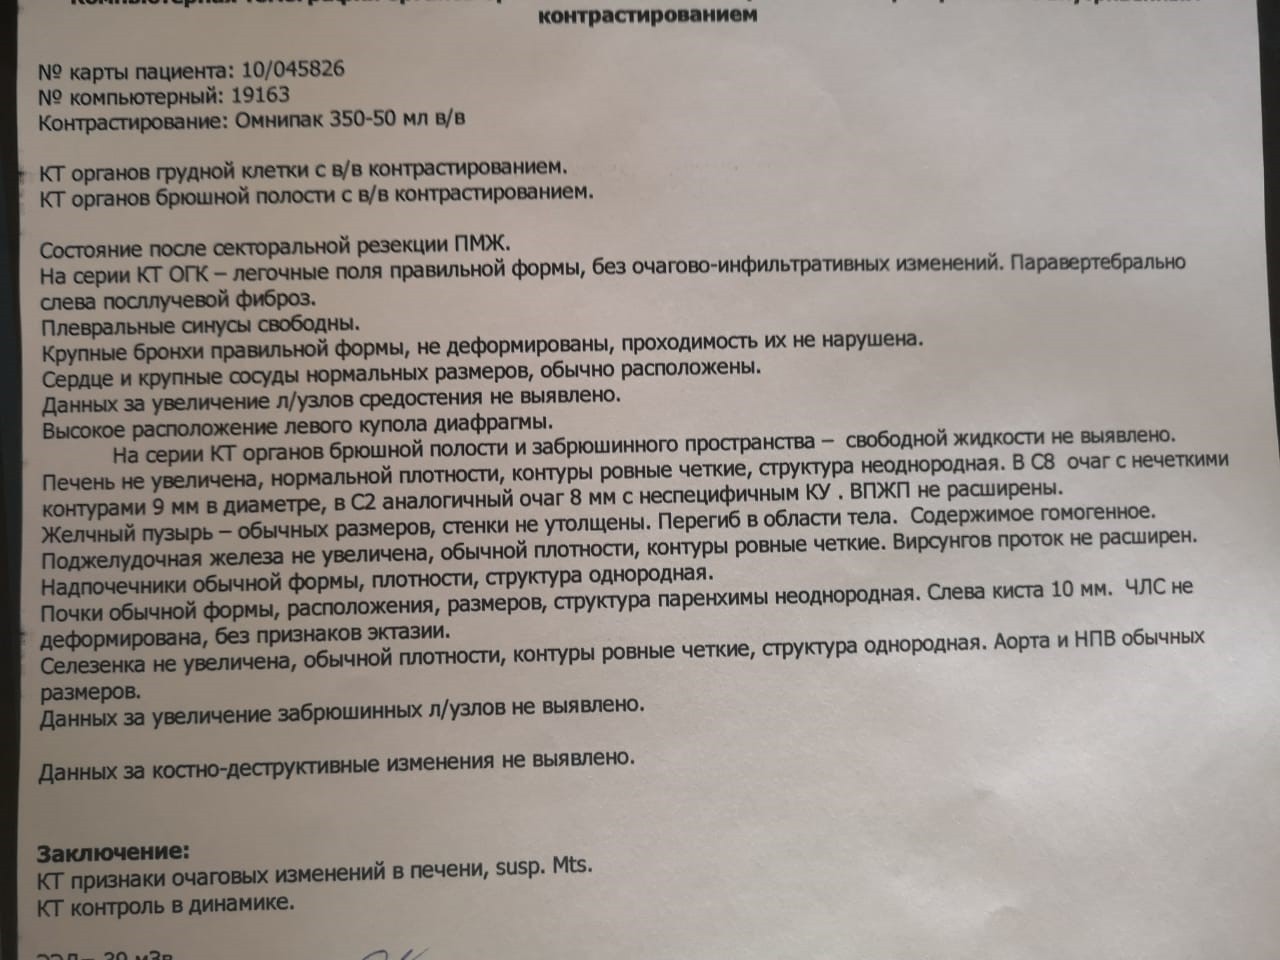

Нормы обзорной рентгенографии брюшной полости